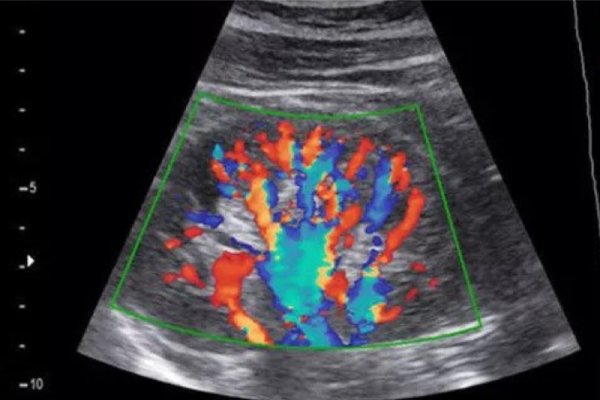

Doppler Ultrasound / Color Doppler Test PCMC

Specialized scan that measures blood flow in arteries, veins, and the placenta. Essential in high-risk pregnancies or vascular conditions.